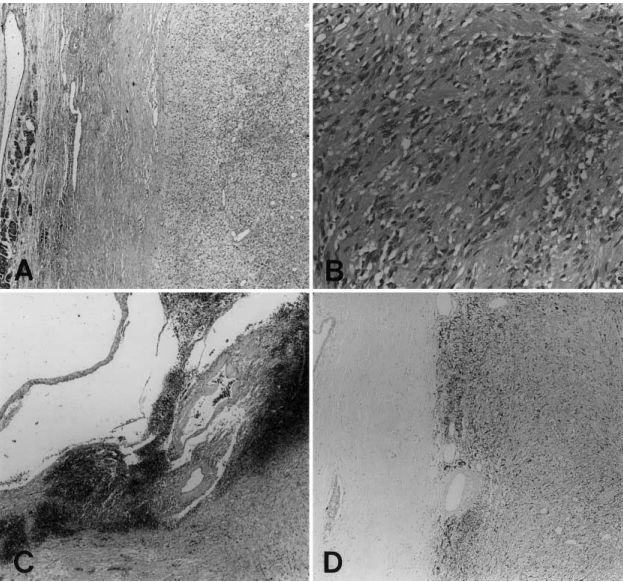

图 3.2(A-D)显微镜下和免疫组化检查结果。肿瘤被纤维组织和正常胰腺实质包围(A,苏木精-伊红,原始放大倍数 ×20),部分由梭形细胞组成,细胞核扭曲和空泡性胞浆化(B,苏木精-伊红,原始放大倍数 ×200)。肿瘤有囊肿形成、出血和血管周围透明化(C,苏木精-伊红,原始放大倍数 ×100)。肿瘤对 S-100 蛋白呈强烈的阳性反应,而周围的胰管则无阳性反应(D,抗 S-100 蛋白,亲和素-生物素-免疫过氧化物酶,原始放大倍数 ×40)